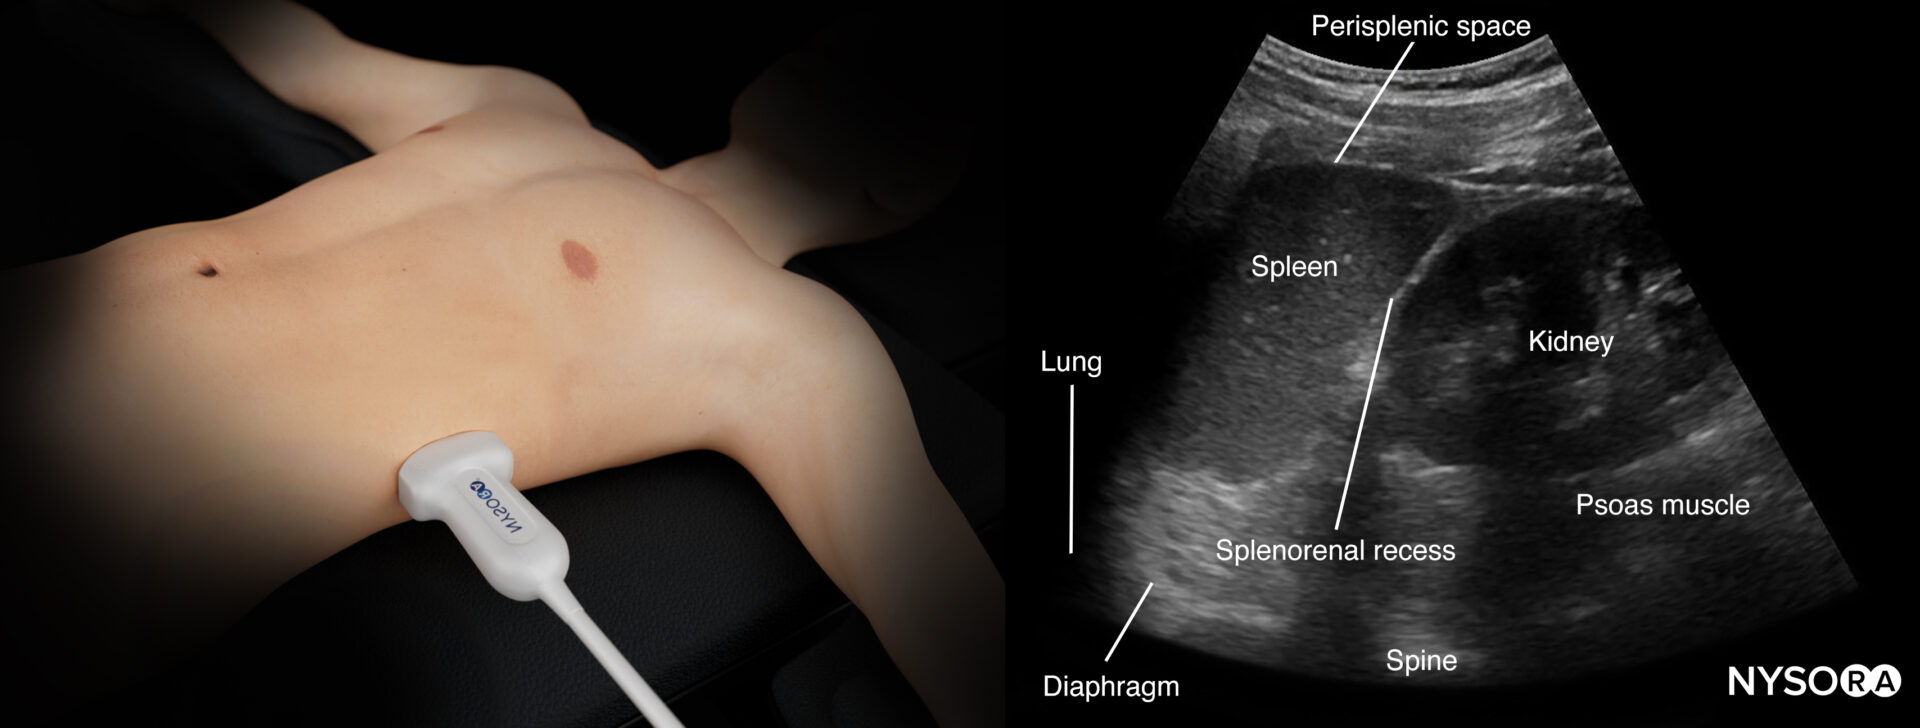

Left upper quadrant (LUQ)

This view allows free fluid assessment in the left thorax and abdomen.

- Position the transducer on the posterior axillary line in the LUQ with the orientation marker toward the head of the patient.

- Start scanning caudally until you visualize the spleen and the kidney.

- Fluid usually accumulates between the spleen and the diaphragm, also called the perisplenic space. Free fluid can also accumulate in other anatomical locations, such as the splenorenal recess.

- Structures of interest: lung, diaphragm, spleen, perisplenic space, kidney

Ultrasound anatomy of the left upper quadrant and relevant anatomical structures.